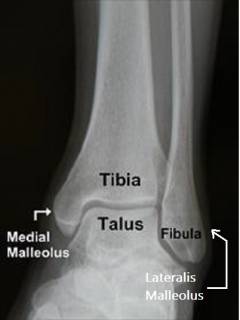

Рис. 1. Схематическое изображение костного компонента голеностопного сустава, вид спереди.

Рис. 6. Рентгенограмма здорового голеностопного сустава, прямая проекция.

Tibia – большеберцовая кость, Talus – таранная кость, Fibula – малоберцовая кость, medialis malleolus – медиальная лодыжка, lateralis malleolus – латеральная лодыжка.